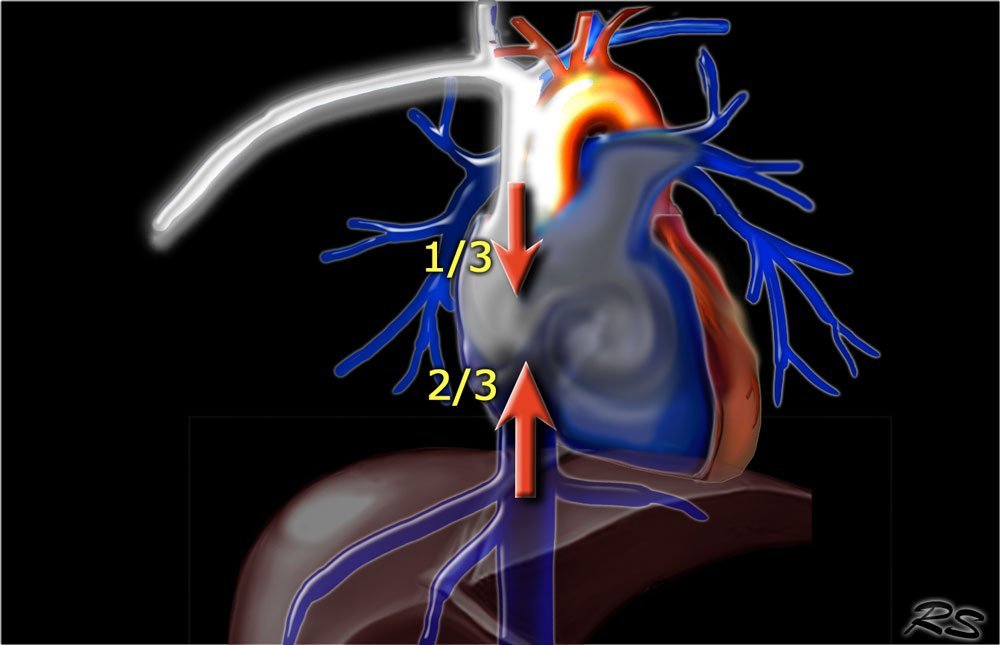

6.1 Transient interruption of contrast

TIC is a flow artefact, that consists of relatively poor contrast enhancement in the pulmonary arteries, while there is good enhancement in the SVC and also in the aorta, which seems not logic at all.

This vascular phenomenon occurs when the patient performs a deep inspiration just before the scan starts, resulting in increased venous return of unopacified blood from the inferior vena cava (IVC). More unopacified blood from the IVC than opacified blood from the SVC enters the right atrium resulting in poor enhancement of the pulmonary arteries.

This phenomanon is especially seen in younger patients, who are capable of deep inspiration.

6.1 Hiện tượng giảm chất tương phản thoáng qua (TIC)

TIC là một ảnh giả do dòng chảy, bao gồm sự ngấm thuốc kém tương đối trong các động mạch phổi, trong khi có sự ngấm thuốc tốt trong tĩnh mạch chủ trên (SVC) cũng như trong động mạch chủ, trông dường như không logic chút nào.

Hiện tượng này xảy ra khi bệnh nhân hít quá sâu trước khi quá trình quét bắt đầu, dẫn đến gia tăng lượng máu chảy ngược trở của máu chưa có thuốc cản quang từ tĩnh mạch chủ dưới (IVC). Nhiều máu chưa có thuốc cản quang trở về nhĩ phải từ IVC hơn so với máu đã có thuốc cản quang từ SVC, dẫn đến sự ngấm thuốc kém của các động mạch phổi.

Hiện tượng này đặc biệt được thấy ở những bệnh nhân trẻ, có khả năng hít thở sâu.

Transient Interruption of Contrast: Deep inspiration results in dilution of contrast in the right atrium by unopacified blood from the inferior vena cava.

Hiện tượng giảm chất tương phản thoáng qua: Hít thở sâu dẫn đến chất tương phản bị hòa loãng với máu chưa có thuốc cản quang từ tĩnh mạch chủ dưới.